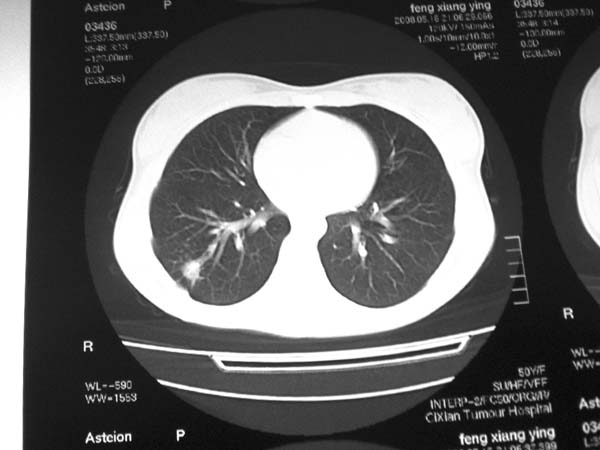

标题: CT13486:F 17Y 咳嗽 咳痰数日请会诊 [打印本页]

标题: CT13486:F 17Y 咳嗽 咳痰数日请会诊

白细胞9600不发烧

考虑右下结核球

右肺下叶结核灶

右下肺背段病灶,考虑结核与炎症鉴别,请进一步检查.

考虑为:右肺下叶外基底段结核球。

结果;痰中找到结核杆菌

痰涂片已找到结核杆菌  将结果告诉大家